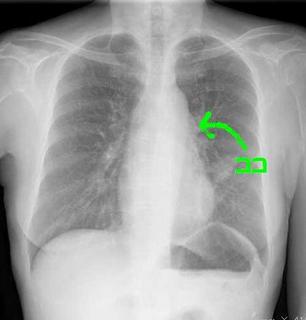

こちらを見て下さい。

わかりにくいかもしれませんが、このあたり。

気管が追いにくい、無くなっているようにも見えます。